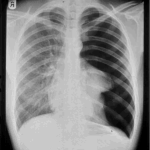

Cigarette smoking is a leading cause of preventable death worldwide. Smoking can cause a wide range of health problems, including lung cancer, heart disease, stroke, and chronic obstructive pulmonary disease (COPD). Smoking also affects the reproductive system, leading to fertility issues in both men and women. It can also harm unborn babies, causing low birth weight and a range of other problems.

One of the most significant risks of smoking is lung cancer. According to the American Lung Association, smoking causes 85% of lung cancer cases in the United States. In addition to lung cancer, smoking can also cause other types of cancer, including throat, bladder, and pancreatic cancer. Smoking can also lead to emphysema, a condition in which the air sacs in the lungs are damaged, making it difficult to breathe.